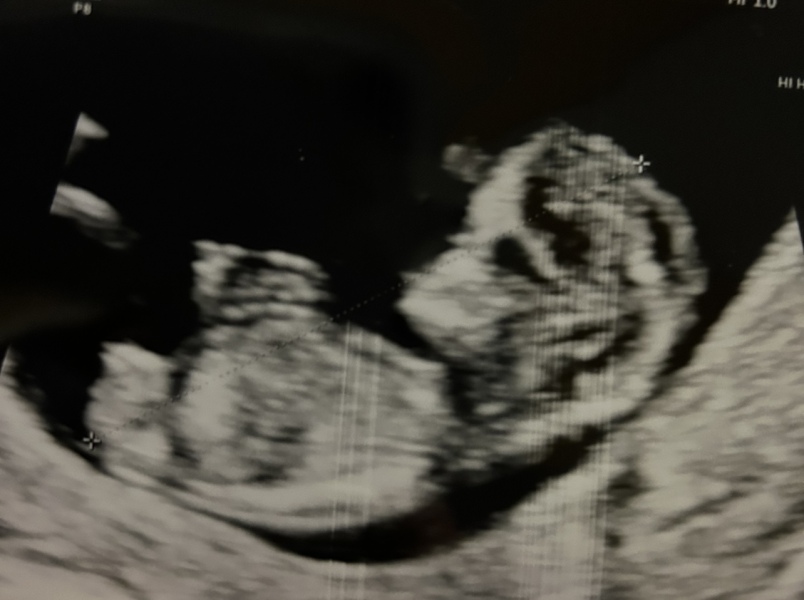

@Thankyouthankyoujellybean got a great scan yday and all going perfectly. Baby was very active!! Measuring 1 day behind just. Can finally breathe!!